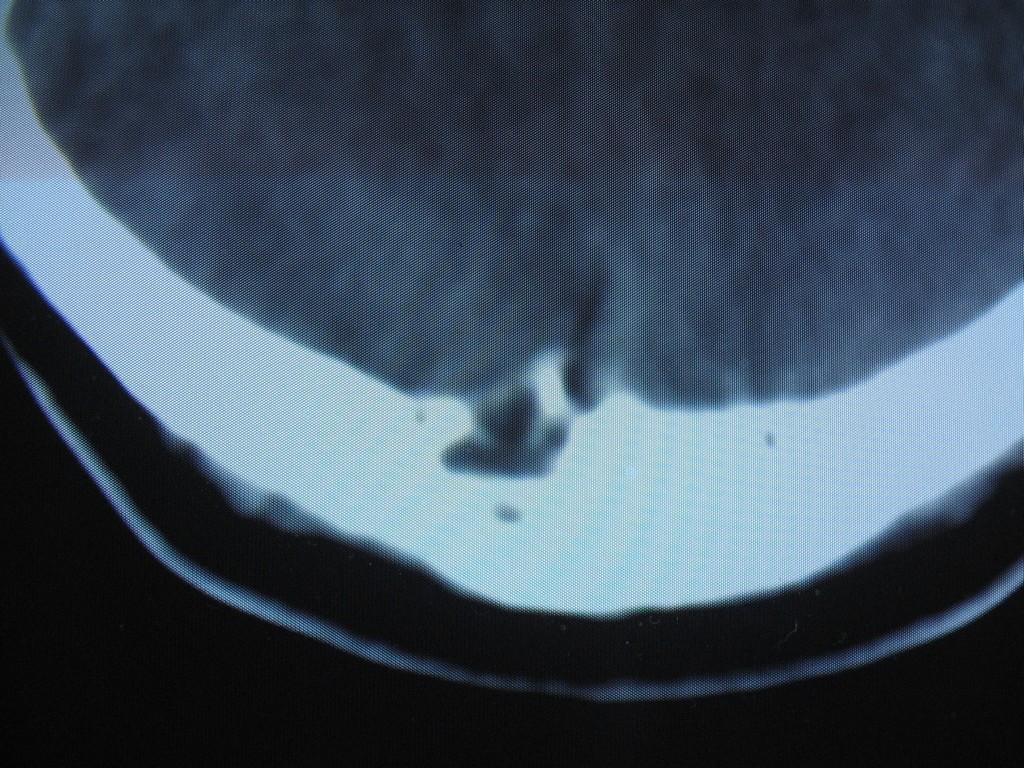

标题: CT22032B:枕骨破坏(从新调整窗宽窗位) [打印本页]

标题: CT22032B:枕骨破坏(从新调整窗宽窗位)

女性病人,53岁,偶尔感枕部针刺样疼痛,ct扫描如下。

蛛网膜颗粒压迹。鉴别:骨巨,嗜酸性肉芽肿,骨髓瘤。

蛛网膜颗粒压迹。

骨巨,嗜酸性肉芽肿,骨髓瘤,动脉瘤样骨囊肿可能

支持蛛网膜颗粒压迹。

支持蛛网膜颗粒压迹,鉴别:骨巨,嗜酸性肉芽肿,骨髓瘤、转移瘤

支持蛛网膜颗粒压迹,嗜酸性肉芽肿发生于30岁以下,基本排除,骨髓瘤、转移瘤多伴有软组织肿块,范围较广。

枕骨蛛网膜颗粒压迹。